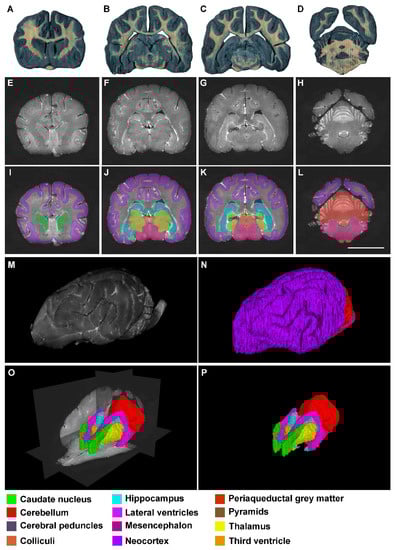

3. Results